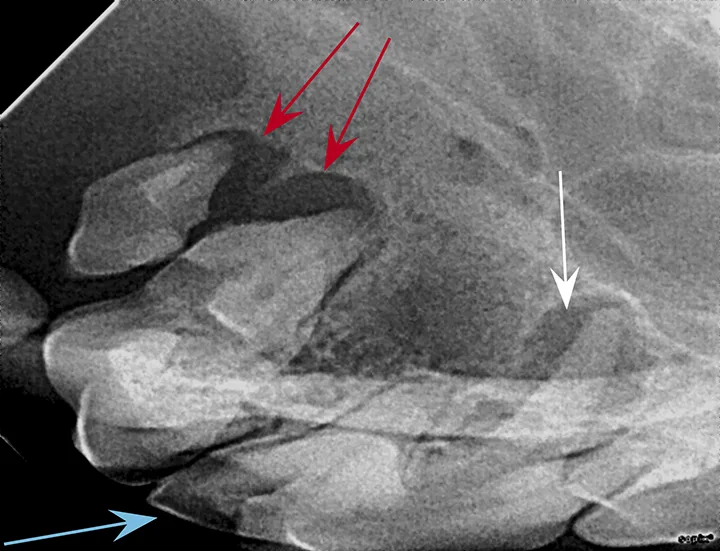

FIGURE 1: Periapical lucency

Periapical lucency develops secondary to bone loss around the tooth root caused by endodontic, neoplastic, or periodontal disease. In this dog, periapical lucency of the maxillary first and second molars (red arrows) developed secondary to periodontal disease. Periapical lucency secondary to endodontic disease (caused by exposure of the pulp from a slab fracture [blue arrow]) is also present surrounding the roots of the right maxillary fourth premolar (white arrow).

Observation of marked mobility of the molars would be expected on anesthetized examination. In this dog, the maxillary fourth premolar would likely not be mobile, as there is still bone surrounding the root apices. Extraction of the maxillary fourth premolar and first and second molars is indicated.